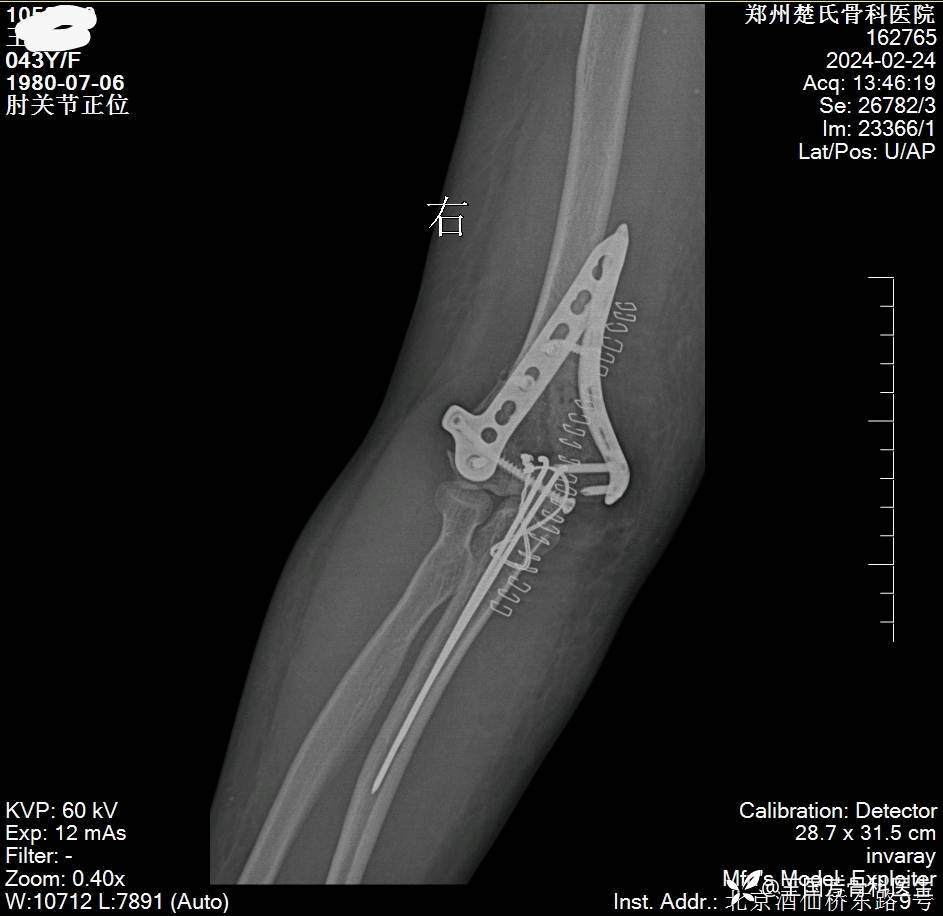

女,43岁,摔倒致右肘肿痛伴活动受限2小时入院。

诊断:肱骨髁间粉碎性骨折

伸直型损伤

Radjn分型:IV型

术后DR、CT